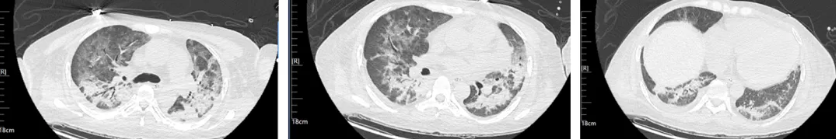

经过治疗后患者病情逐渐好转,呼吸机需氧浓度及PEEP逐渐下调,复查血气氧和指数逐渐好转,9月17日复查胸部CT(见图4),氧合指数165,予拔除气管插管,改日间高流量(流速 40L/min,氧浓度60%)与夜间无创呼吸机辅助通气(IPAP12cmH2O EPAP 5cmH2O FiO2 45%)交替,复查血气氧和指数P/F 182。予逐渐下调氧浓度复查氧和指数进一步升高(见图5),监测患者外周血感染指标超敏C反应蛋白降至基本正常(见图6)。调整鼻导管吸氧,10月7日复查胸部CT双肺慢性及间质改变较前明显吸收(见图7)。监测患者外周血KL-6水平较前明显下降(见图8)。

图7:患者2025年10月7日复查胸部CT